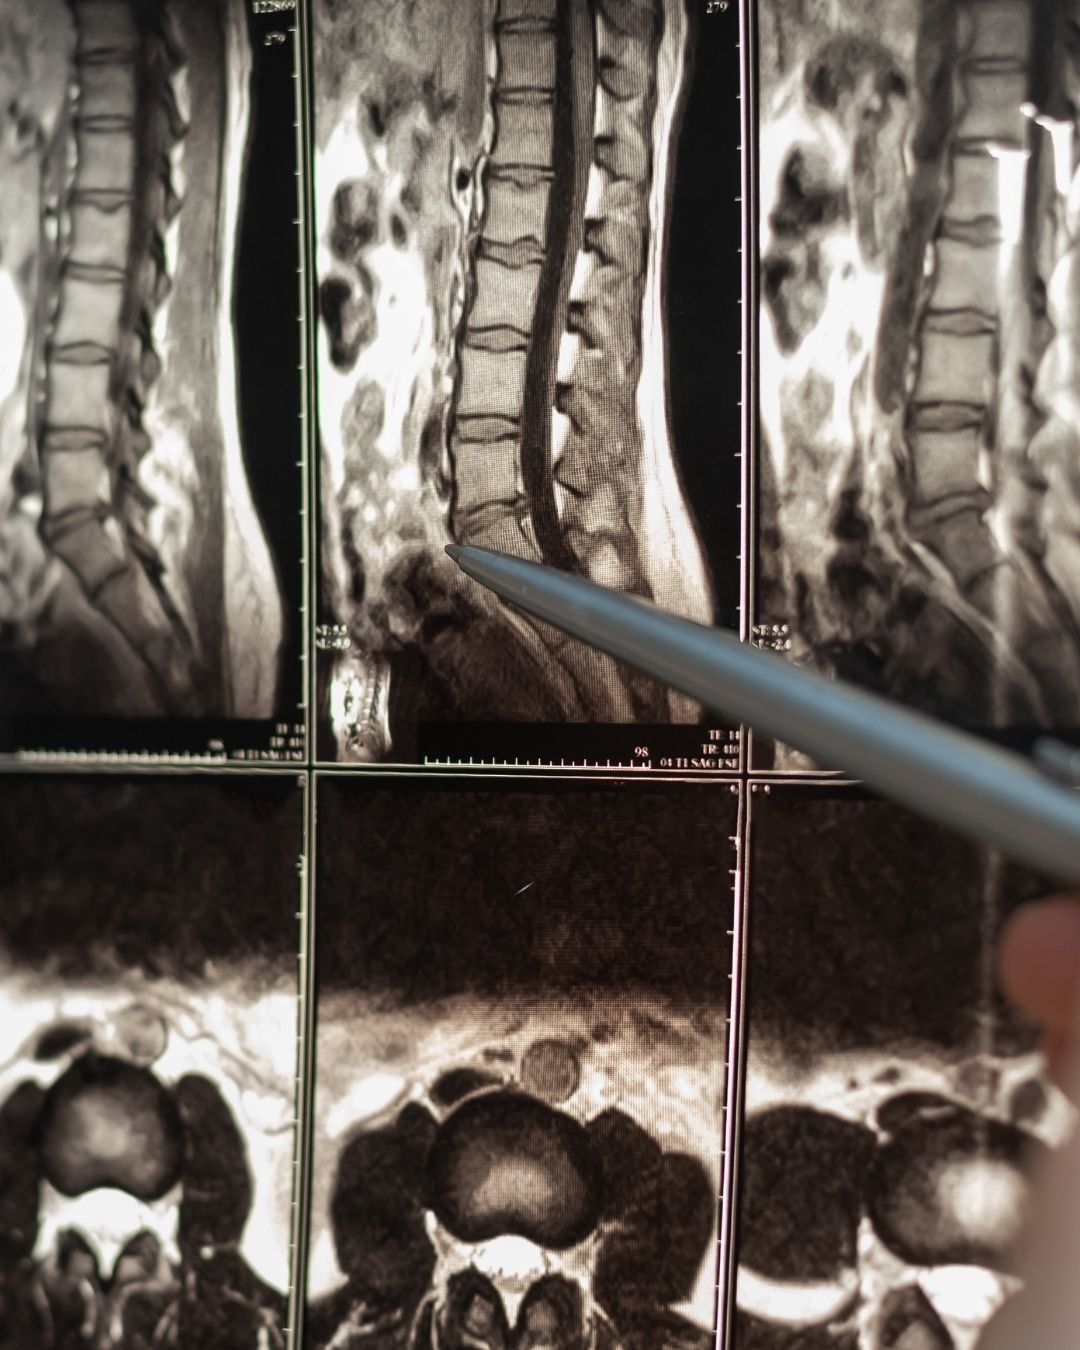

"Lomber BT", tıpta "Lomber Bilgisayarlı Tomografi" anlamına gelir. Bu, bel bölgesinin (lomber omurga) bilgisayarlı tomografi (BT ya da CT) yöntemiyle görüntülenmesidir. Omurganın alt kısmındaki yapıları detaylı şekilde incelemek için kullanılır.

🧠 Lomber BT'de Ne Görülür?

• Omurlar (bel kemikleri)

• Diskler (omurlar arası yastıkçıklar)

• Spinal kanal ve sinir kökleri

• Yumuşak dokular (kaslar, bağlar vs.)